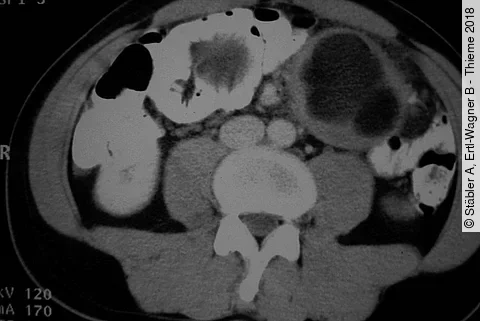

Stäbler A, Ertl-Wagner B - Thieme 2018

Ein 52-jähriger Patient stellt sich mit Übelkeit und Gewichtsabnahme und krampfartigen Bauchschmerzen vor. Was fällt Ihnen in der CT nach oraler und i. v. Kontrastmittelgabe auf?